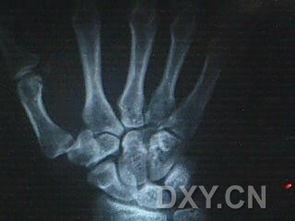

手骨骨折图片,影像学诊断与治疗策略

3. 影像学检查:如X光片、CT等,可以清晰地显示骨折部位和程度。

4. 手骨骨折图片:医生可能会参考一些手骨骨折图片,以便更好地了解骨折情况。